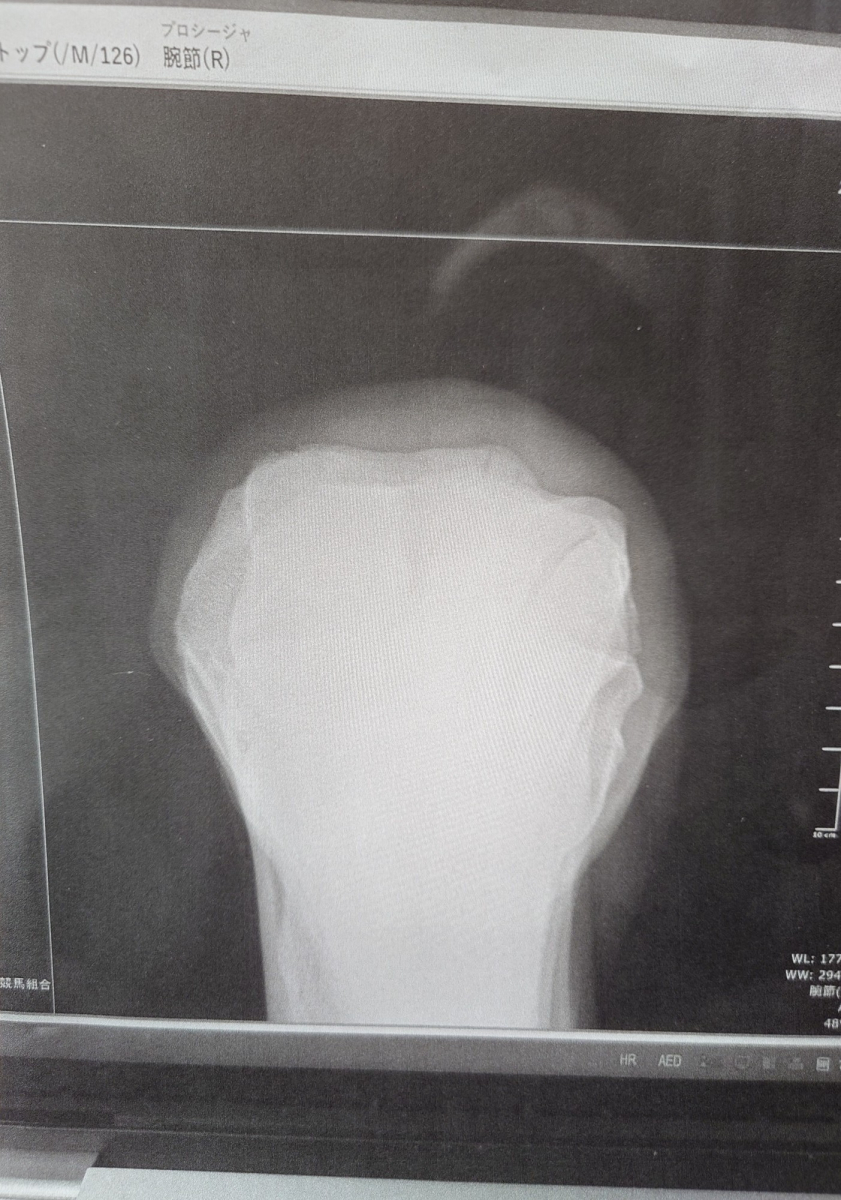

本馬は2025年2月2日に東京ダート1600mの3歳新馬戦でデビュー。中団待機からラストはメンバー最速の上がりタイムをマークして猛追し、0秒1差の3着まで追い上げました。2戦目の中山ダート1800m戦では果敢に先行しましたが、早めに後退してしまい11着に大敗。レース中に右前橈骨遠位端骨折を発症していたことが判明し、骨片除去手術を実施。9号見舞金を受給し、この一戦を最後にJRAの登録は抹消。大井へ移籍しています。

ところが、この一戦後に右膝の骨膜剥離が確認されました。勝った直後のタイミングとはなりますが、休養がベストとなったこともあり、頭数整理のためにオークションに出品させていただきます。

【本馬についての現状説明】

右ひざは保存で歩様確認し、競馬を使うことも可能ですが、休養も必要との所見です。また、検査は受けていませんがノドの異音を確認しています。ただ、乗った騎手の話ですと、レースでは影響ない感じとのことでした。(大井競馬小林・坂井英光調教師)

※2025年4月6日の競走で右前橈骨遠位端骨折発症。骨片除去手術を実施。事故見舞金9号(競走中の事故により事故発生の日から6ヵ月以上中央競馬の競走に出走できなくなった場合)を受給しています。